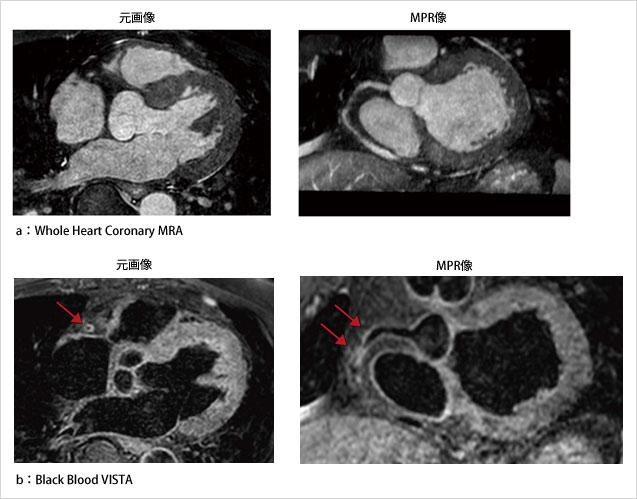

■ Black Blood VISTA

VISTA(Volume ISotropic TSE Acquisition)は,3D Turbo Spin Echoの等方性ボクセルで撮像するために最適化された撮像シーケンスであり,T1強調,T2強調,プロトン密度強調などの多彩なコントラストを得ることが可能である。

循環器領域におけるVISTAの臨床応用では,Black Blood Imagingとしての利用が期待されている。従来のBlack Blood法は,Dual IR法を用いた2D収集のため,撮像範囲に制限があった。それに比べ本法は,リフォーカシングパルスの最適化により,血液信号を抑制しつつ,高い空間分解能で画像を取得できる。これにより,冠動脈を各任意方向から観察可能である(図4)。また,T1強調,T2強調ともに撮像することで,プラークの性状評価の可能性も期待される。

図4 Black Blood VISTA

(画像ご提供:東京警察病院様)